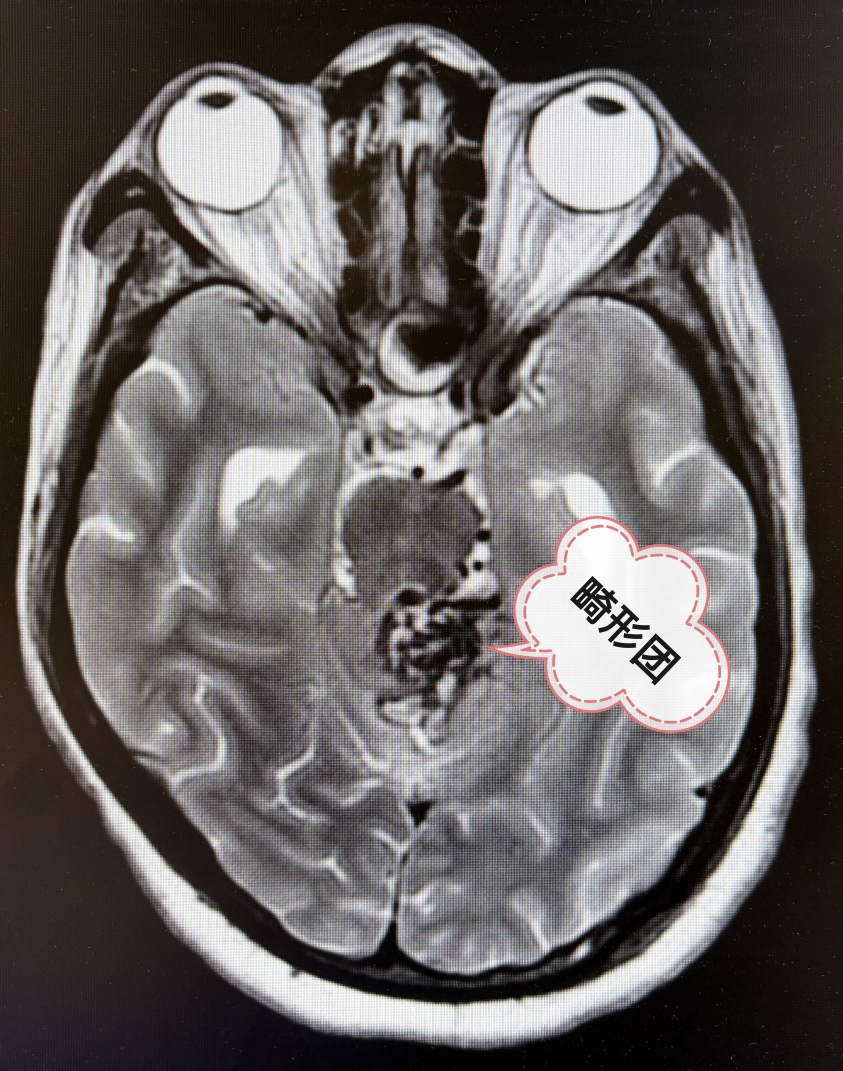

2期术前MRI

畸形团